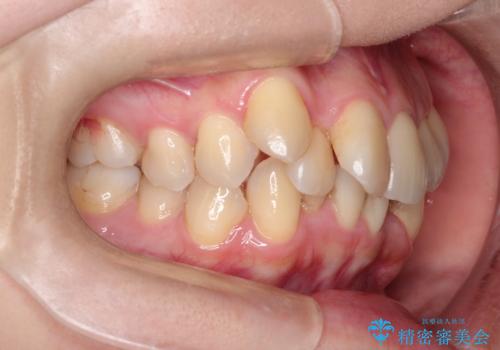

ガタガタの抜歯矯正を裏側ワイヤーを使っての目立たない矯正

- ハーフリンガル

- 八重歯とガタガタを主訴に来院されました。

目立たないワイヤー矯正を希望されたので、上下左右のはを1本ずつ抜歯して、ハーフリンガル(上顎だけ裏側)にて矯正をすることにしました。